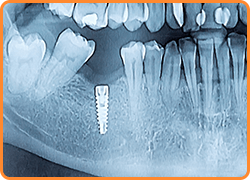

インプラントとは、歯を失った部分にチタン製の人工歯根を埋め込み、その上から人工歯を装着する治療方法です。

人工歯根は顎の骨としっかりと結合するため、入れ歯のようにズレや外れることを気にせずに食事や会話を楽しむことができます。

また、ご自身の健康な歯を削る必要がないので安心して治療を受けていただけます。

インプラントは、フィクスチャー(人工歯根)とアバットメント(連結部分)と上部構造(人工の歯)で構成されています。

顎の骨にしっかり埋め込むので、ご自身の歯のような感覚です。

レントゲンでは確認することのできない骨の状態や神経なども、3D画像で確認することができます。

正確な治療計画の立案で、安全・安心の治療をご提供いたします。